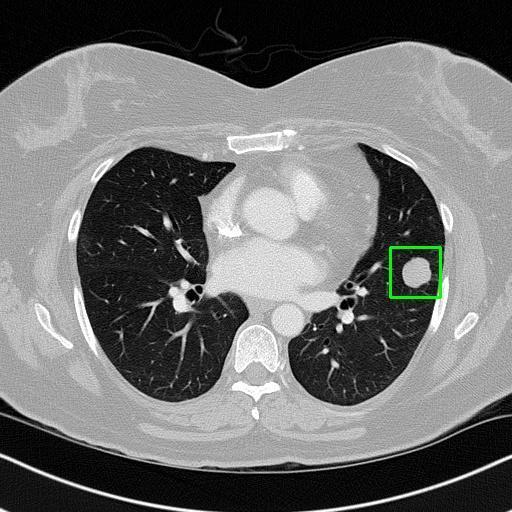

We developed an AI-based system using deep learning models for analyzing lung CT scans to detect and classify pulmonary nodules. We chose the YOLOv11 architecture for its enhanced object detection capability and adapted it specifically for medical imaging, incorporating pixel-level precision and severity classification.

Classification into three severity levels with colored bounding boxes.

Maintaining performance on small, complex features like micro-nodules tested the limits of traditional object detectors.

Designed a severity classification system that categorizes nodules into null, moderate, and severe using colored bounding boxes, assisting in rapid clinical decision-making.